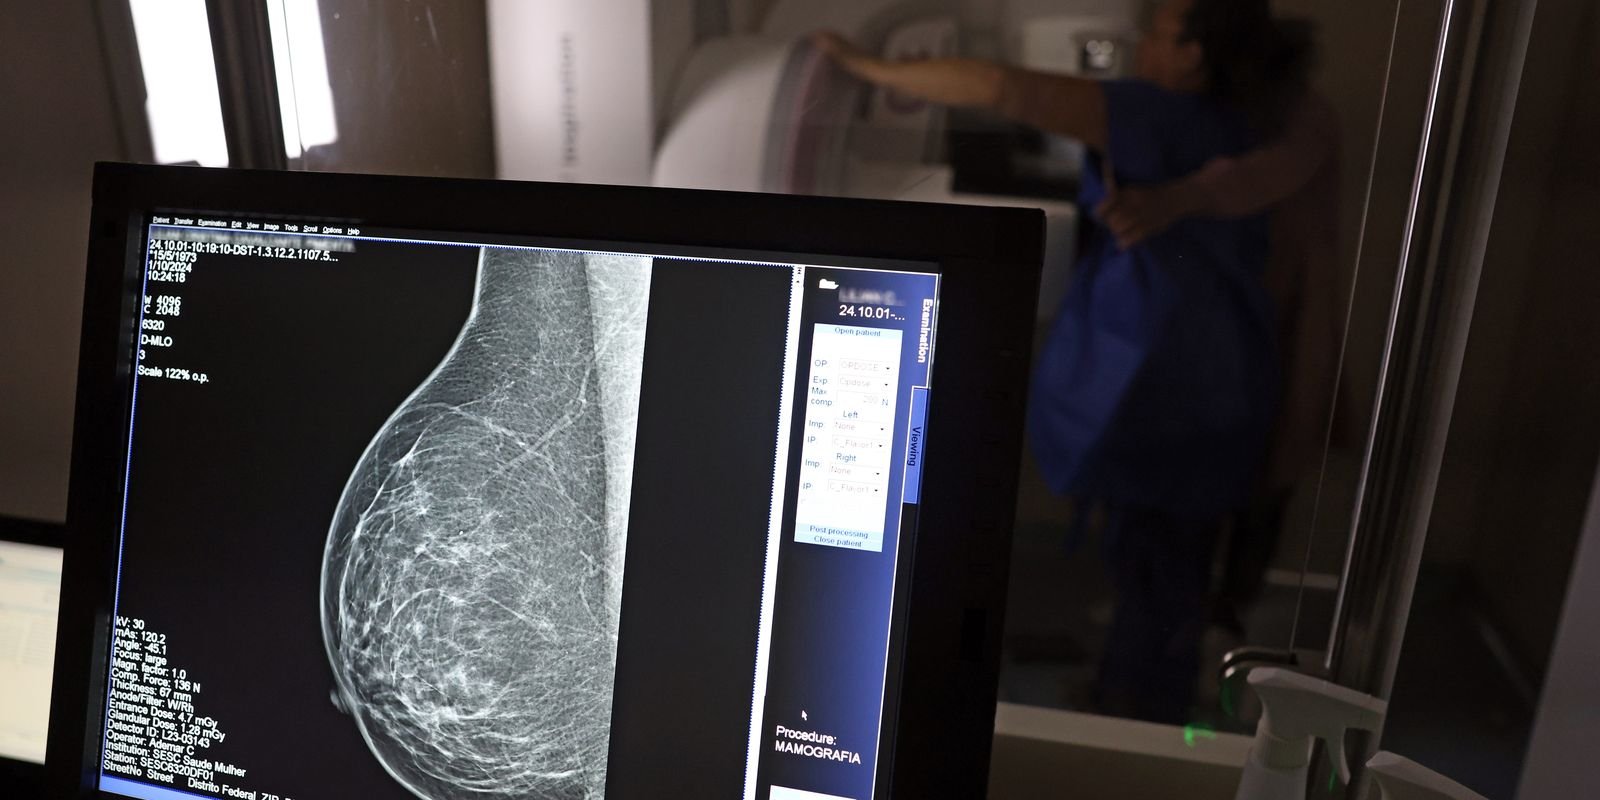

No mês de conscientização sobre o cancro de peito, um relatório destaca a valia de chegada igualitário ao rastreamento e tratamento da doença. Segundo o Atlas da Radiologia no Brasil, do Escola Brasílico de Radiologia e Diagnóstico por Imagem (CBR), o chegada aos mamógrafos ainda é um duelo.

O país tem 6.826 equipamentos registrados, sendo 96% em funcionamento. Metade deles está disponível no Sistema Único de Saúde (SUS), responsável por atender 75% da população. Isso equivale a 2,13 mamógrafos por 100 milénio habitantes dependentes do SUS.

Na saúde suplementar, que cobre 25% da população, o cenário é mais favorável: 6,54 aparelhos por 100 milénio beneficiárias, quase o triplo da rede pública. O Acre exemplifica essa disparidade — são 35,38 mamógrafos por 100 milénio habitantes na rede privada, contra 0,84 no SUS.

Há disparidades regionais. Roraima tem a menor proporção (1,53 por 100 milénio), seguida do Ceará (2,23) e Pará (2,25). A Paraíba lidera o ranking (4,32), primeiro do Província Federalista (4,26) e do Rio de Janeiro (3,93).

O Brasil tem uma cobertura muito baixa de mamografias: 24%. O ideal recomendado pela Organização Mundial da Saúde é de 70%. Mesmo em lugares porquê o estado de São Paulo, que tem a maior concentração de mamógrafos do país, a taxa gira em torno de 26%.

Em setembro, o Ministério da Saúde ampliou as diretrizes de rastreamento, recomendando que mulheres entre 40 e 49 anos realizem mamografias, mesmo sem sintomas. De conciliação com o Instituto Pátrio do Cancro (Imca), mais de 73 milénio mulheres recebem o diagnóstico de cancro de peito anualmente no Brasil.

“O que é efetivo na redução da mortalidade é você desvendar o tumor antes de ter sintoma galeno. Quanto menor o tumor, melhor para a gente desvendar o tratamento e maior a chance de tratamento. E a gente só consegue fazer isso com exames de imagem”, diz Ivie.

Ela explica que no caso de diagnóstico de um cancro de peito com menos de 1 cm, a chance de tratamento é de 95% em cinco anos, independentemente se ele é do tipo mais ofensivo. “E esses tumores só vão ser detectados na mamografia. Essas pessoas que têm que ir fazer mamografia são mulheres saudáveis. Não são mulheres doentes”, acrescenta.